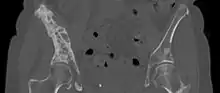

![]() | |

| 3D rendered CT scan of bone metastases of the hip bone, in a 60 year old woman with parotid gland cancer. Large lesions are seen on the ilium on the more distant side. Involvement of the vertebral column has caused a compression fracture. | |

CT Scan

A CT scan can detect bone metastases before they present with symptoms in patients diagnosed with tumors that are high-risk for spread to the bone. Even sclerotic bone metastases are generally less radiodense than enostoses, and it has been suggested that bone metastasis should be the favored diagnosis between the two for bone lesions lower than a cutoff of 1060 Hounsfield units (HU).[10] If a biopsy is indicated, a CT scan is often used to localize the lesion before biopsy.[14]